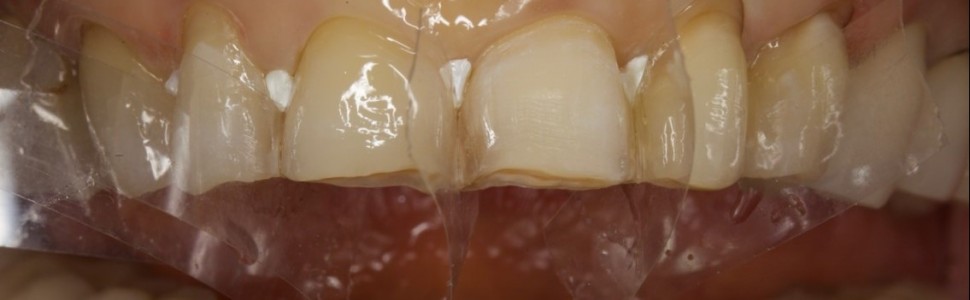

Odbudowy kompozytowe posiadają przewagę nad uzupełnieniami pełnoceramicznymi w licznych sytuacjach klinicznych. Takie leczenie jest mniej kosztowne, zwykle mniej inwazyjne, a odbudowy mogą być poddawane korektom i naprawom w dowolnym momencie. Jeśli jednak odbudowana ma zostać większa liczba zębów, metodą bezpośrednią, warstwową, polegającą na odbudowie każdego zęba z osobna, może to być bardzo czasochłonne i wymagające dużego nakładu pracy. W takich sytuacjach świetną alternatywą jest technika Flow Injection (czasem zwana także techniką wtrysku płynnego kompozytu). Jest ona minimalnie inwazyjna, nadaje się jako tymczasowe lub stałe rozwiązanie problemów związanych ze starciem zębów i nieregularnym kształtem, a także jest szybka do przeprowadzenia w warunkach klinicznych.